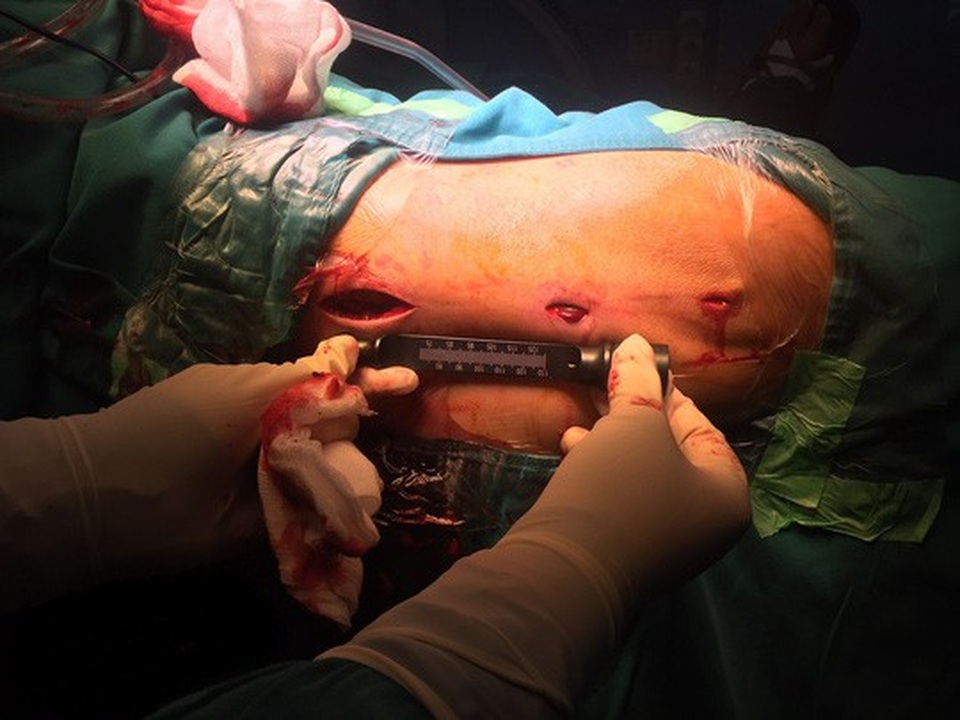

Ngày 27-11, Bệnh viện Chấn thương Chỉnh hình TP HCM cho biết vừa phẫu thuật bắt đinh vít bảo tồn thành công khớp háng cho một cụ ông bị trượt chân té tại nhà.

Qua hội chẩn, các bác sĩ xác định đây là 1 trường hợp gãy liên mấu chuyển có thể mổ bảo tồn, giữ lại khớp háng thật cho ông. Sau khi giải thích cho người nhà, ê kip phẫu thuật Khoa Chấn thương Chỉnh hình đã quyết định phẫu thuật chọn dụng cụ đinh kết hợp xương đầu gần xương đùi mới nhất để phẫu thuật cho ông.

Theo BS Nguyễn Huy Toàn, thành viên ê kíp phẫu thuật, ưu điểm của loại đinh này là đường mổ nhỏ (chỉ cần 3 vết rạch da dài 2-5 cm) không mở ổ gãy nên xương dễ lành, ít mất máu, ít đau hơn so với các phương pháp truyền thống. Ngoài ra, thiết kế loại đinh này rất vững chắc, ngay ngày hôm sau có thể cho phép bệnh nhân đi chống chân chịu lực. Với các ưu điểm này, giúp người bệnh có thể ngồi dậy sớm, ra khỏi giường bệnh, giảm áp lực chăm sóc lên người nhà.